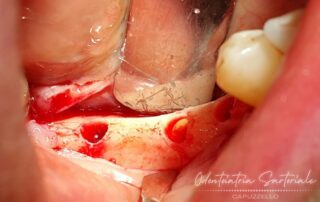

Dima chirurgica

Quando è necessaria una programmazione implantare estremamente precisa e protesicamente guidata, si ricorre all’utilizzo di una dima chirurgica (rif. foto 3) che guida l’operatore al corretto posizionamento delle viti in titanio.

Questo si ottiene andando a incrociare in un sistema digitale 3D i dati di tac e programmazione protesica.

In foto potete osservare tutti i passaggi.